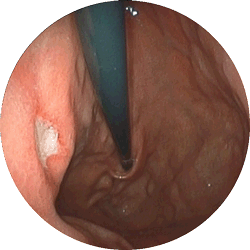

食道潰瘍内視鏡

食道潰瘍

心窩部の痛み、胸やけ、飲み込むときの胸の痛みで来院

内服薬1ヶ月で治癒